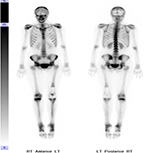

While FDG is an analog of glucose, the fluoride in NaF incorporates into the hydroxyapatite (mineral component) of bone by replacing a hydroxyl group to form fluoroapatite. F18-NaF PET bone scan commonly demonstrate non-malignant, scattered focal uptake within the spine, bilateral knees, feet and shoulder joints, consistent with degenerative bone remodeling. Normally, there is no brain uptake on NaF PET scanning.

A) Whole-body F18-FDG PET scan maximum intensity projection (MIP) bone demonstrates intense uptake in the brain and renal excretion. Mild activity is seen within the bone marrow. B) Whole-body F18-NaF PET bone scan maximum intensity projection (MIP) demonstrates scattered focal uptake within the spine, bilateral knees, feet and shoulder joints consistent with degenerative bone remodeling. Note: Intense uptake is seen within the brain on FDG PET and no uptake is seen on NaF PET. |